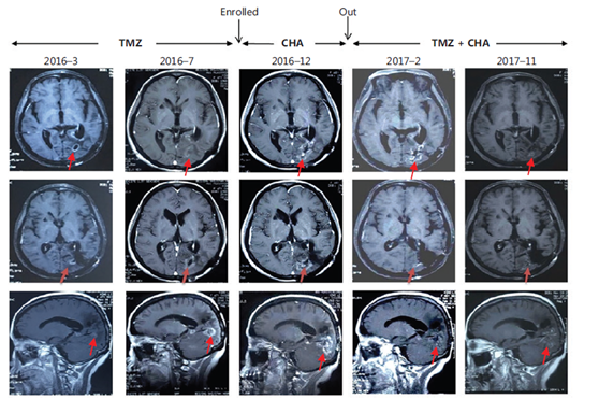

治療惡性腦膠質(zhì)瘤Ⅰ期臨床研究特殊病例分析:注射用綠原酸有效延長受試者生存期,并能一定程度解除受試者對替莫唑胺的耐藥現(xiàn)象

受試者入組時(shí)替莫唑胺耐藥且疾病進(jìn)展;

使用注射用綠原酸后病情得到有效控制,出組后再次使用替莫唑胺治療,MRI結(jié)果顯示替莫唑胺再次起效。

患者采用替莫唑胺與注射用綠原酸交替使用、聯(lián)合治療的方案,顱內(nèi)病灶目前已完全消失,從確診至今,生存期已超過13年。

病例圖片來源 Kang, Z. ,  Li, S. ,  Kang, X. ,  Deng, J. ,  Yang, H. , &  Cheni, F. , et al. (2023). Phase Ⅰ study of chlorogenic acid injection for recurrent high-grade glioma with long-term follow-up. 癌癥生物學(xué)與醫(yī)學(xué):英文版, 20(6), 465-476.